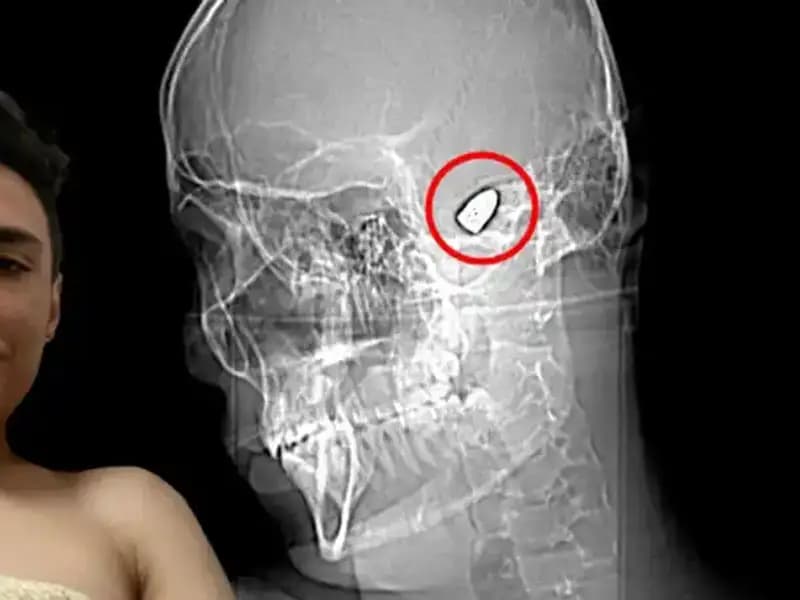

Kafasında Patlayıcı Var: Psikolojik Sorunları ile Savaşan Bir GençGenç yaşında ciddi ruhsal sorunlarla boğuşan bir gencin hikayesi ve toplum üzerindeki etkileri.